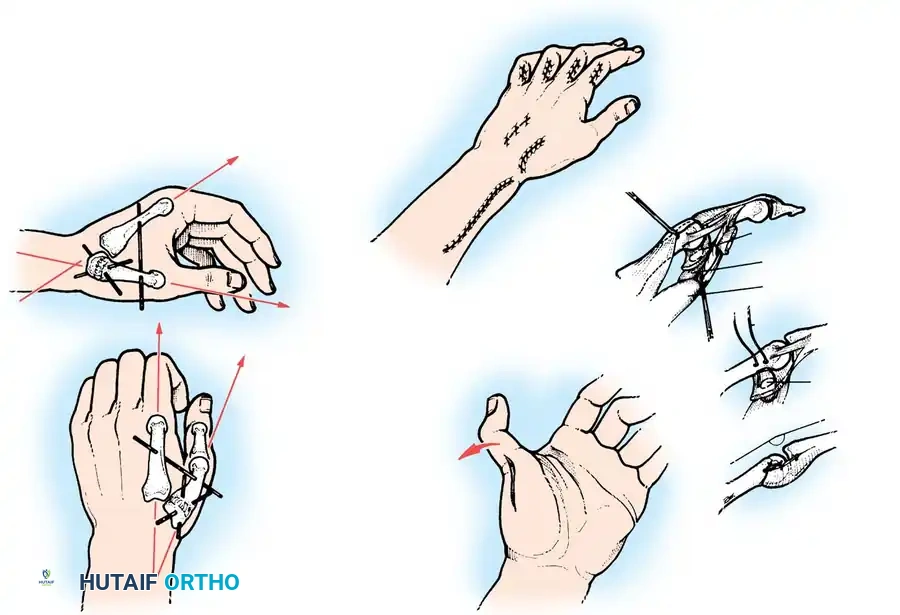

Moberg Key Grip Procedure

For Group 1 or Group 2 tetraplegics, the Moberg key grip procedure is foundational. This involves:

1. FPL Tenodesis: The FPL tendon is divided proximally and anchored to the distal radius. As the patient actively extends the wrist, the anchored FPL passively tightens, driving the thumb into lateral pinch against the index finger.

2. Thumb CMC Arthrodesis or Stabilization: To prevent the thumb from collapsing into retropulsion during pinch, the carpometacarpal (CMC) joint is often arthrodesed, or the metacarpophalangeal (MCP) joint is stabilized via capsulodesis or arthrodesis.

Intrinsic Balancing and the Zancolli Lasso

Tetraplegic hands are inherently "intrinsic-minus," leading to clawing of the fingers (hyperextension of the MCP joints and flexion of the IP joints). This posture defeats the tenodesis effect, as the fingers roll up into the palm rather than sweeping in a wide arc to grasp objects.

To correct this, the Zancolli lasso procedure or similar intrinsic stabilizations are performed. The Flexor Digitorum Superficialis (FDS) tendons are divided distally, looped around the A1 or A2 pulleys, and sutured back onto themselves. This creates a static volar tenodesis that prevents MCP hyperextension, ensuring that proximal pull on the FDP translates into a functional sweeping grasp.

For Hand and Wrist Reconstructions:

1. The hand is immobilized in a bulky dressing and volar splint with the wrist in neutral to slight extension, MCP joints flexed to 70 degrees, and IP joints fully extended.